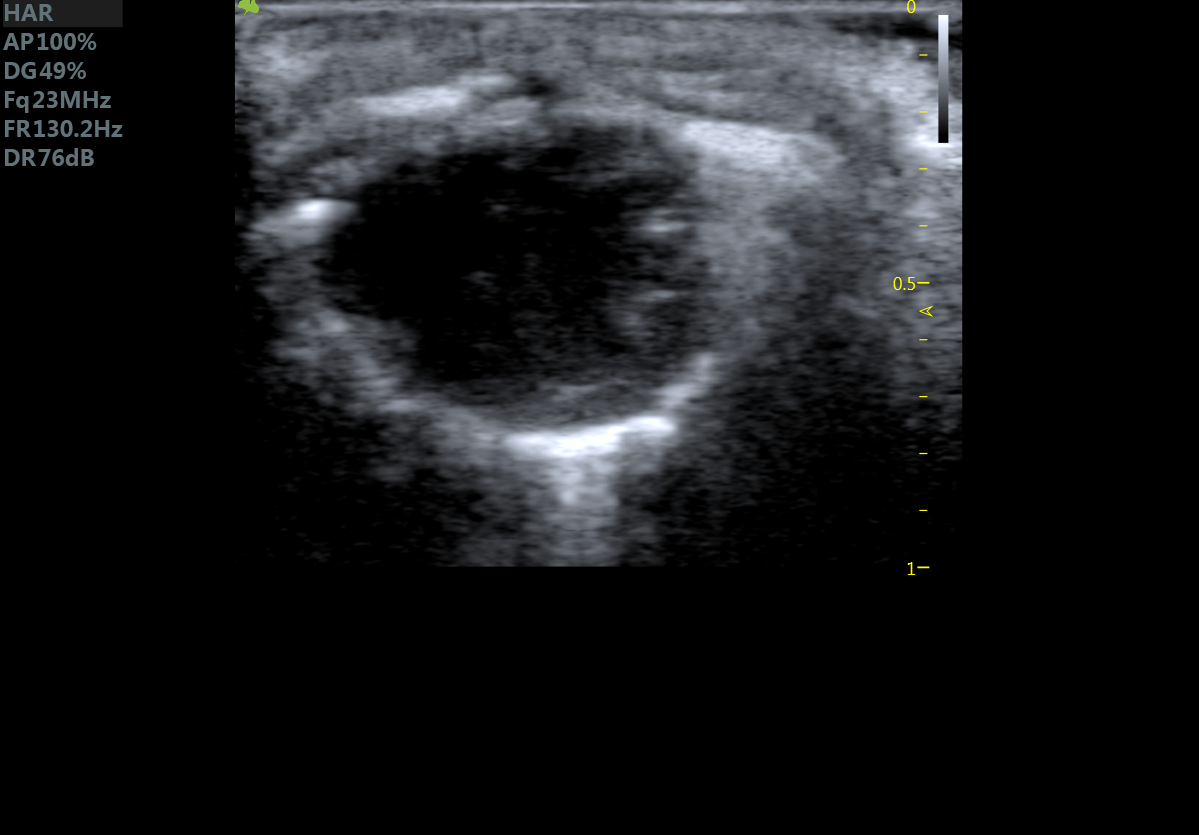

23MHz高频探头,优秀卓越的浅表显影

RF Flow充盈不外溢 Xcen超高频浅表显影

小鼠长轴M型 小鼠短轴M型

小鼠长轴B型 小鼠短轴B型